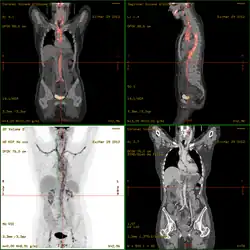

- 18F-fluorodeoxyglucose positron emission tomography/computed tomography (FDG-PET/CT)has become a widely used imaging tool in patients with suspected Large Vessel Vasculitis, due to the enhanced glucose metabolism of inflamed vessel walls.[38] The combined evaluation of the intensity and the extension of FDG vessel uptake at diagnosis can predict the clinical course of the disease, separating patients with favourable or complicated progress.[39]